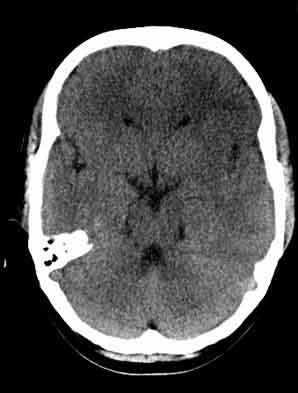

患者,女,29,头痛呕吐2月余,已建议增强或mri进检。

额叶低密度影,建议增强。

左额叶白质密度减低,考虑脑炎,建议增强或mri .

左侧额叶见低密度影,边界模湖 建议 增强 除外占位

双侧脑室前角、旁周围白质低密度减低,边界模糊不清,患者女性:大胆推测,脑白质脱髓鞘改变。mri检查

左侧额叶见低密度影,边界模湖,考虑脑炎, 建议增强除外占位.